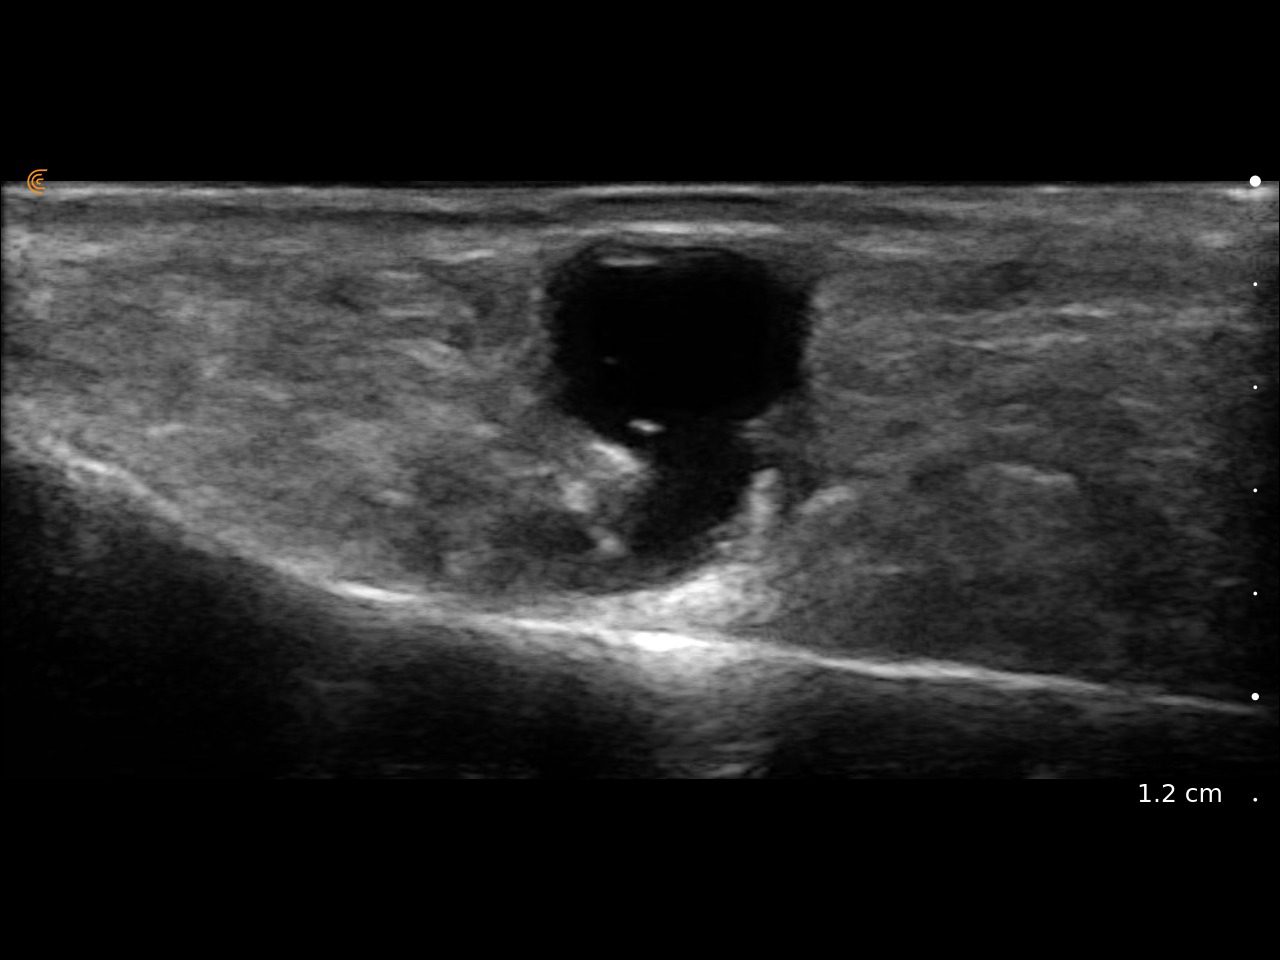

Visualize targets in real time to deliver PRP or cortisone—even in complex joints. Instantly diagnose sprains, tears, and effusions, and make confident decisions about surgical intervention

Visualize targets in real time for precise nerve blocks and corticosteroid injections—reducing injectate volumes and boosting safety, confidence, and patient outcomes.

Assess synovitis, enthesitis, and monitor treatment efficacy with high-resolution ultrasound, enabling precise, real-time joint and soft tissue evaluation, accurate needle guidance, and improved confidence in clinical decision-making.